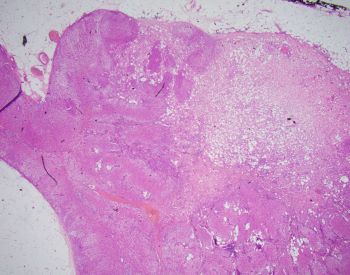

On histologic examination, this nodule consisted of adrenal cortical adenoma admixed with canalicular and tubular (gland like) structures. Tubular structures were typically characterized by flat cells. Some of the cells exhibited vacuolated cytoplasm resembling signet ring cells.

Adenomatoid tumor is a benign neoplasm of mesothelial origin that is generally seen in paratesticular adnexa, uterus and fallopian tubes. This entity has also been described in other organs including the adrenal gland.

In light of the morphologic and immunohistochemical findings, the diagnosis of composite adrenal cortical adenoma and adenomatoid tumor was rendered.